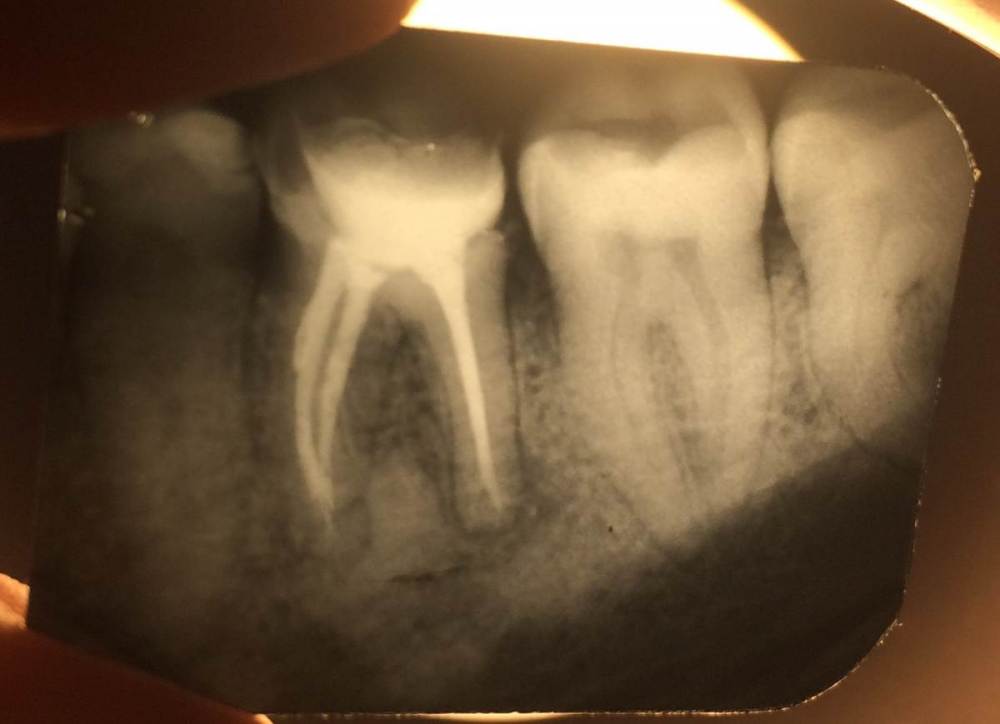

lodo4nik Опубликовано 7 июля, 2020 Поделиться Опубликовано 7 июля, 2020 Добрый день! Прошу помочь с решением судьбы зуба.На панорамном снимке мой стоматолог обнаружил новообразование в районе 36 зуба. Говорит причина в плохо залеченном канале-не вычистили все до конца при лечении.Этот зуб лечил около 10-15 лет назад (сейчас мне 35) в городской гос. поликлинике. Жалоб на него никаких нет и не было-не болит, не реагирует на холодное/горячее, выделений в районе зуба нет.Для уточнения сделали точечный рентген.Мой стоматолог советует зуб удалять и через пол года ставить имплант-т.к. будем сохранять зуб-сохраним новообразование. Сейчас это доброкачественное образование, которое со временем может перерасти в злокачественное. Во втором медцентре-хирург однозначно сказал удалять.В третьем медцентре сказали, что зуб можно спасти, но для уточнения отправили на КЛКТ. Посмотрели и сказали, что это киста и она уже очень разрослась-зуб под удаление, не спасти.Отправил снимки в четвертый медцентр, в столице (сам я живу в областном центре), знакомый посоветовал их-сказал что сохранили зуб, когда все остальные врачи настаивали на удалении. Оттуда пришел ответ-приезжайте, перепломбируем каналы, сохраним зуб. Но они КЛКТ не смотрели.Я в растеряности-что делать. Помогите окончательно определиться.И еще дополнительный вопрос. У меня повышен С реактивный белок высокочувствительный последние лет 8, не значительно, но постоянно 1.5-2.5 (референс <1) . Причина может быть в этом зубе?Ссылка на КЛКТ:https://yadi.sk/d/bVoEJ3dM53D3CAАрхив с КЛКТ:https://yadi.sk/d/YkVkCMyxDQsXQAФото без сжатия:https://yadi.sk/d/_LrW1Gt7YADgFQЗаранее спасибо! Ссылка на комментарий

red_butler Опубликовано 9 июля, 2020 Поделиться Опубликовано 9 июля, 2020 Я в растеряности-что делать. Помогите окончательно определиться. Здравствуйте, новообразования нет, это банальный периодонтит, для принятия решения нужно очно или по фотографии оценить оставшийся объем твердых тканей, если зуб возможно восстановить, то повторное лечение корневых каналов, если нет, то удаление 2 Ссылка на комментарий